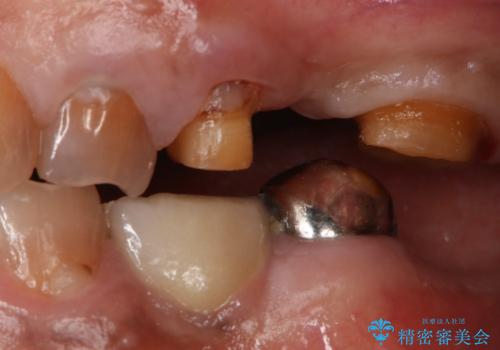

- 左上臼歯部に保険のブリッジを入れていたがすぐに取れてしまったので自費治療でのやり変えを希望された患者様です。

インプラントとブリッジを提案しましたが時間をかけたくないとのことだったので、ブリッジでの治療を選択しました。

左上6番が大きく傾いているため、露髄や痛みが出る可能性を事前にお伝えしています。